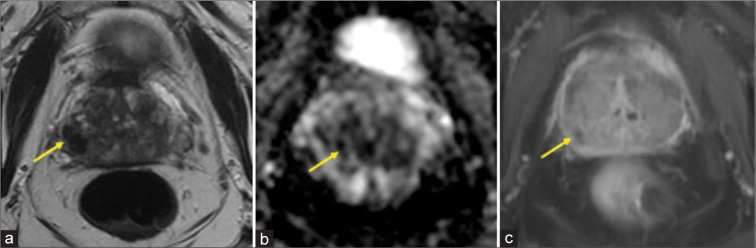

Idiopathic granulomatous mastitis is a rare, chronic inflammatory disease of the breast of uncertain etiology that can mimic breast cancer. In rare instances, it may emerge secondary to trauma to the breast. We present a case of a 66-year-old woman who initially underwent a benign stereotactic core-needle biopsy of her left breast complicated by a small hematoma which initially remained unchanged mammographically and sonographically for 1 year; then, it enlarged unexpectedly at the 21-month interval follow-up prompting an ultrasound-guided biopsy revealing granulomatous mastitis.

Abstract Image